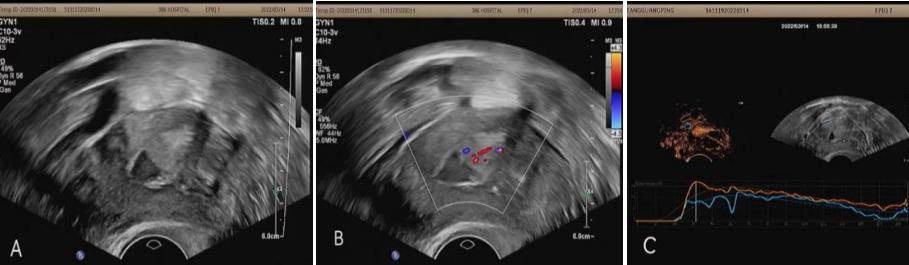

病例1:女,59岁,主因“绝经10年,阴道出血2天”入院。常规超声见宫腔内高回声,大小约1.5x1.0 cm。超声造影显示宫腔病灶左侧壁早于子宫肌层先显影,迅速灌注,呈弥漫高增强。晚期造影剂不均匀消退,早于子宫肌层,周边呈低增强,内部呈持续等增强。超声造影提示:宫腔内占位性病变(恶性不除外)。手术病理:子宫内膜样腺癌。